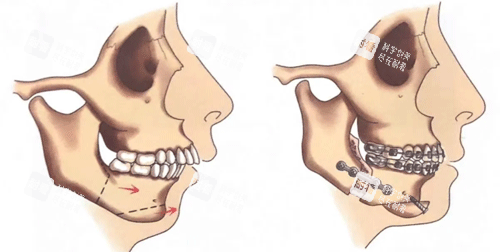

万启龙的“正畸-正颌联合治疗”,核心就俩字:“配合”。术前正畸先通过牙套调整牙齿位置,把“歪七扭八”的牙排整齐,消除牙齿的“代偿性倾斜”(比如地包天患者为了咬合,下牙会故意往前长);术中正颌再精细切割、移动颌骨,把“错位的骨头”摆回正位;术后正畸然后“微调”,让牙齿和骨头理想贴合,咬合稳如“齿轮”。

28岁的小王是典型的“凸嘴+下巴后缩”,侧面看像“月亮脸”,拍照必须抿嘴,否则像在“生气”。万启龙给她的方案是:术前正畸1年,用隐形牙套把上牙往回收、下牙往前拉;术中采用“上颌LeFortⅠ型截骨+下颌矢状劈开术”,把上颌骨往后推3毫米,下颌骨往前移5毫米;术后正畸3个月,调整牙齿咬合。

万启龙的方案更“狠”:术前正畸1年半,用固定矫治器把上牙“拉”出来、下牙“压”回去;术中采用“上颌LeFortⅠ型截骨+下颌矢状劈开术+颏成形术”,把上颌骨往前推5毫米,下颌骨往后退7毫米,同时调整下巴形态;术后正畸6个月,精细调整咬合。

万启龙的方案是“精细打击”:术前正畸8个月,用直丝弓矫治器调整牙齿轴向;术中采用“单侧下颌矢状劈开术”,只切割左边下颌骨,把它往后移3毫米,同时用3D打印导板辅助定位,确保骨头移动“不偏不倚”;术后正畸4个月,关闭剩余间隙。